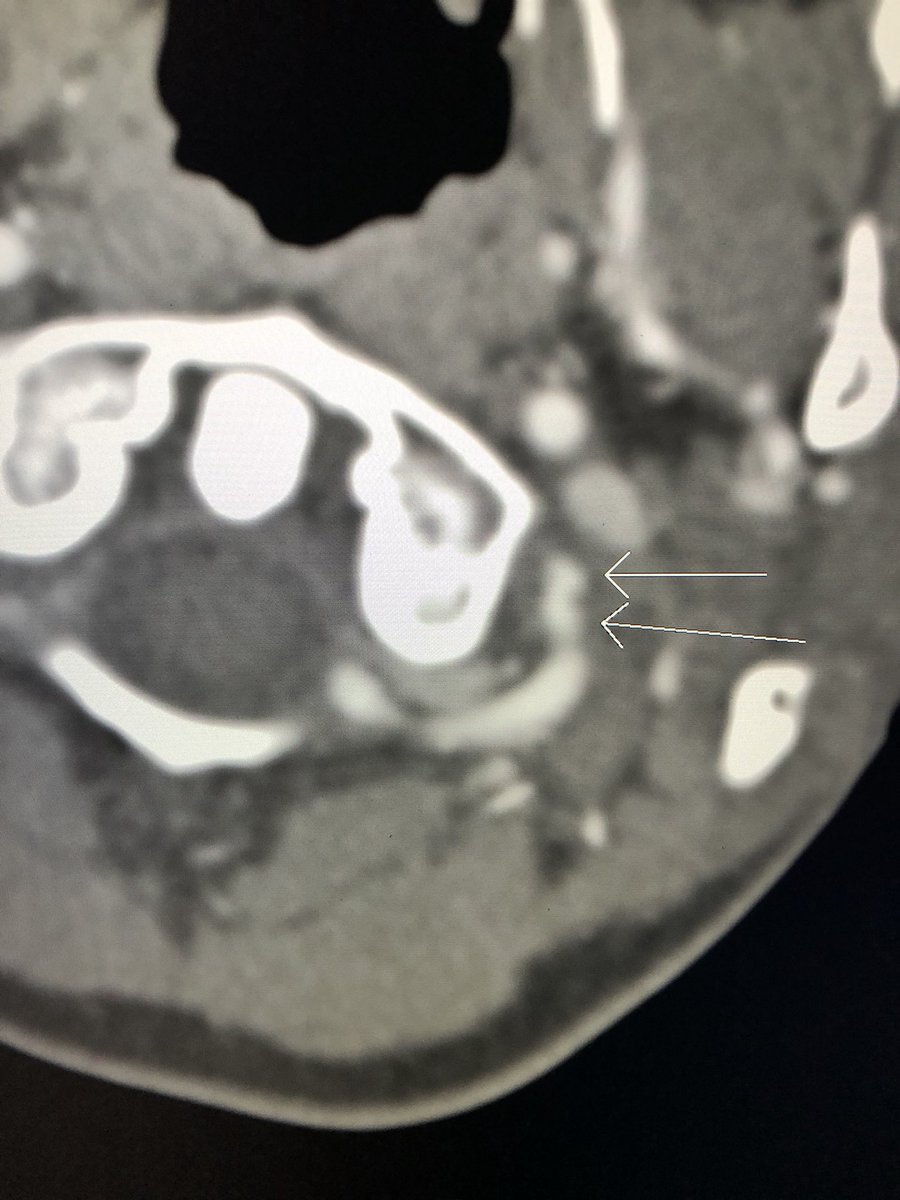

Una disección de la arteria vertebral, después de "tronarse" el cuello con un quiropráctico 😱😱😱 vía Rishi Seth, MD Por cierto, los quiroprácticos no son #Médicos, y mucho menos, científicos, aunque avalen colchones por aquí y por allá.